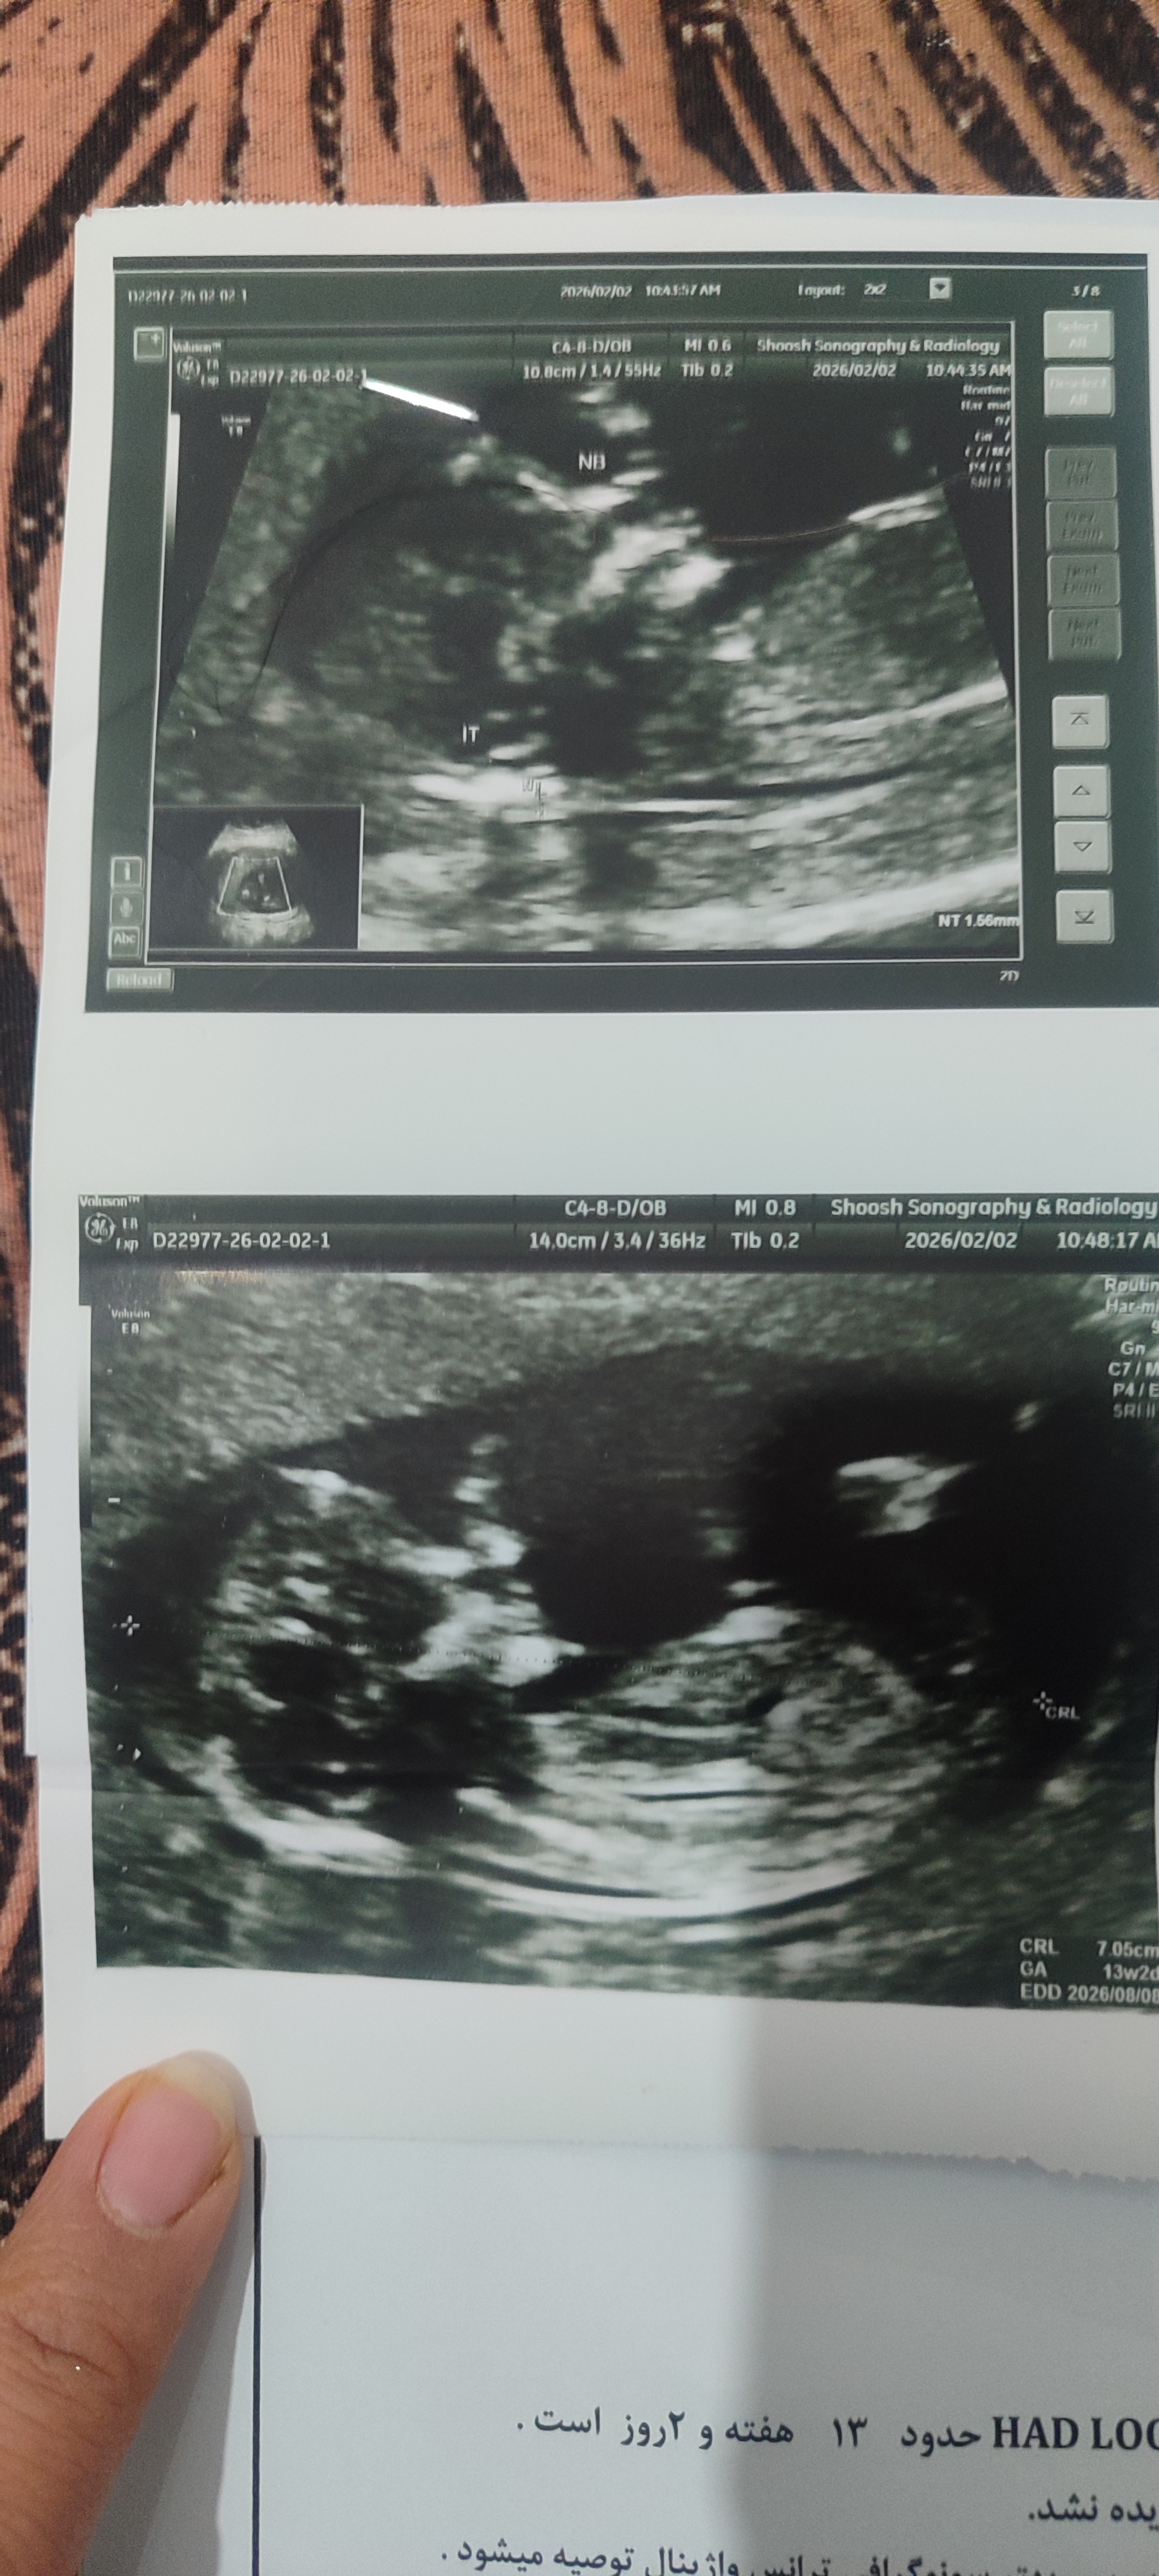

دوتا دختر دارم دکتر گفت شانس دختر بودنش بیشتره خیلی دوست داشتم پسر باشه خودم یکم شک دارم

۱۸هفته مشخص میشه. برا جاریم گفته بودن احتمالا پسر ک شد دختر.